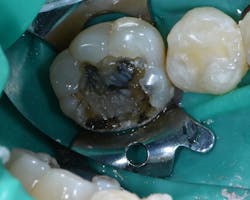

Figure 4: After initial amalgam removal. Note recurrent decay.

Figure 6: G-ænial Bulk Injectable (GC America) A2 being used to fill majority of preparation